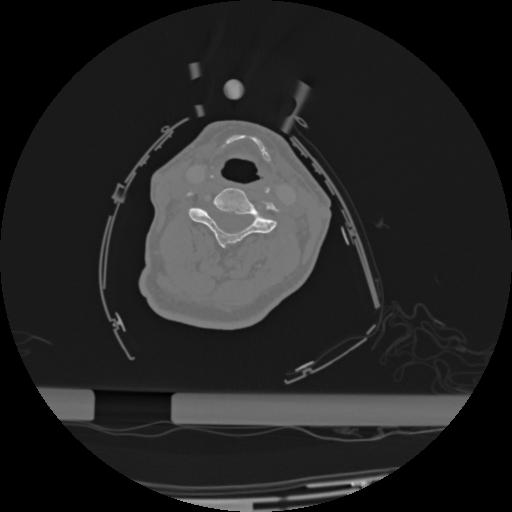

22 ANGIO,CE,Vol,0.5,ANGIO,,